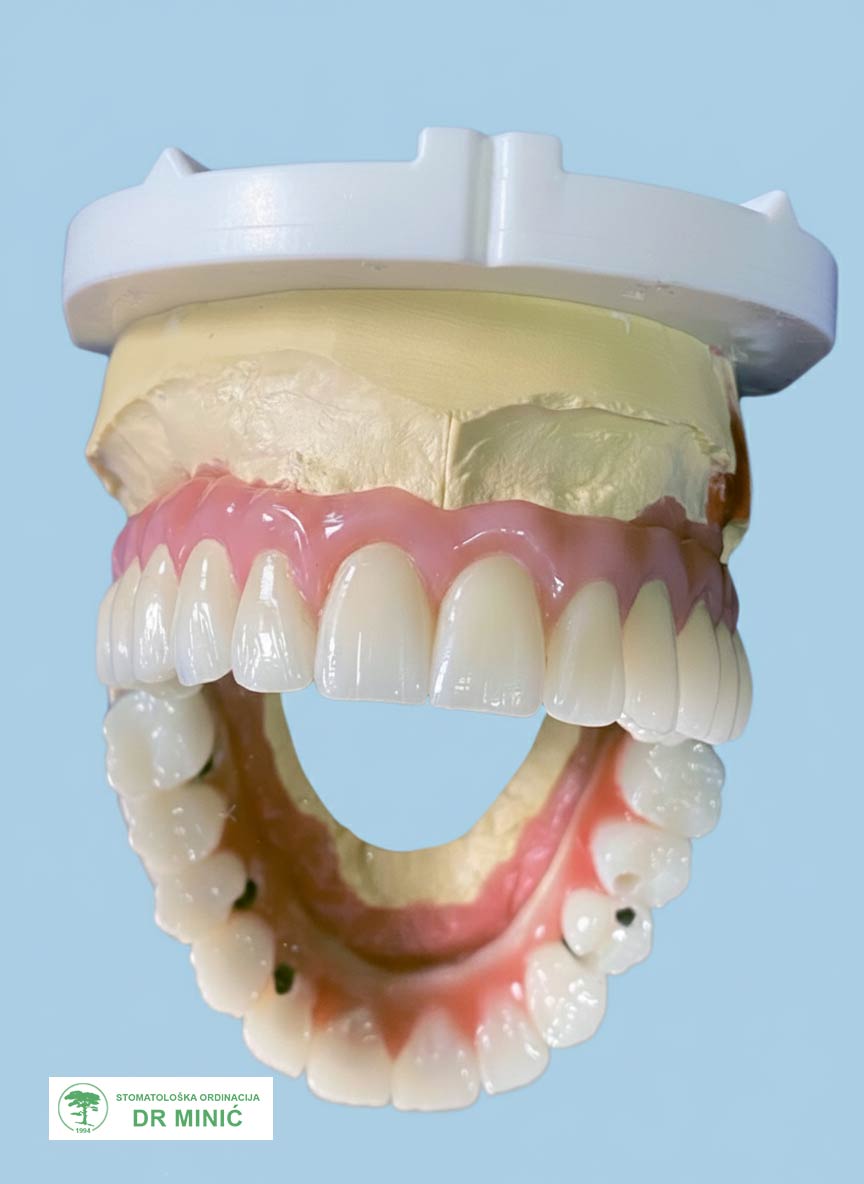

Druga faza – privremeno rešenje

Dok se čeka da implantati srastu sa kosti (u narednim mesecima), pacijentu je urađen privremeni rad, kako bi imao funkcionalne i estetske zube u tom periodu.

Treća faza – izrada trajnog rada

Nakon četri meseca započeta je izrada trajnog protetskog rada:

• Uzet je precizan otisak vilica.

• Napravljen je plastični model budućih zuba, koji je poslužio za procenu izgleda i funkcije.

• Zatim je urađena metalna (titanijumska) konstrukcija (prečka) na koju su kasnije postavljeni zubi.

• U više proba proveravani su izgled, položaj i stabilnost rada.

• Na kraju je izrađen završni rad sa maskom koja imitira desni i sve je cementirano u ustima.